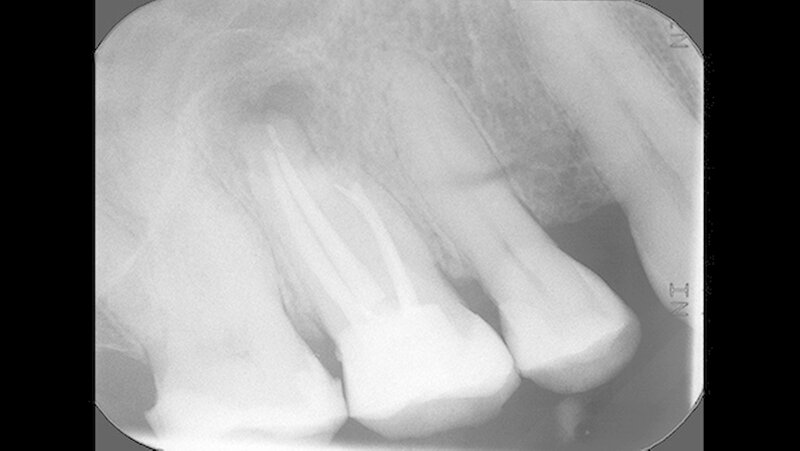

Um die mesiobukkale Wurzel freizulegen, wurde der Knochen darüber entsprechend entfernt (Abbildung 2) und eine Wurzelspitzenresektion an der mesiobukkalen Wurzel Zahn 16 durchgeführt. Das Granulationsgewebe konnte vollständig entfernt werden und wurde für eine histopathologische Untersuchung eingeschickt.